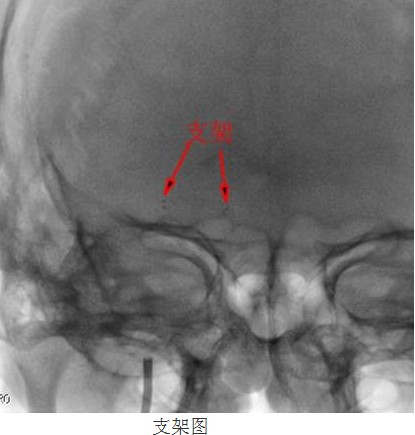

常規(guī)準(zhǔn)備后,神經(jīng)內(nèi)科顏津津主治醫(yī)師在助手高彬醫(yī)師配合下采用Seldinger法穿刺股動(dòng)脈,置導(dǎo)管鞘、引導(dǎo)管,在導(dǎo)絲帶引下將導(dǎo)引導(dǎo)管放置右側(cè)頸內(nèi)動(dòng)脈巖部造影,后在透視下,順著造影路圖,小心將微導(dǎo)絲、微導(dǎo)管通過狹窄處并置入右側(cè)大腦中動(dòng)脈M3段,接著撤出微導(dǎo)管,順著微導(dǎo)絲置入Gateway球囊, 至狹窄部位,經(jīng)造影骨性標(biāo)志等多重定位后證實(shí)球囊位置良好,接壓力泵緩慢加壓擴(kuò)張,撤出球囊造影,顯示血管成形良好。選取Wingspan支架, 順微導(dǎo)絲將支架輸送器小心送至狹窄處,造影定位確認(rèn)支架位置準(zhǔn)確覆蓋狹窄部位,釋放支架,撤出支架輸送器,造影證實(shí)血管狹窄處成形良好,觀察10分鐘后再次造影,支架無移位,狹窄處遠(yuǎn)端血管完整,未見血管狹窄、造影劑外滲。撤除導(dǎo)絲、導(dǎo)引導(dǎo)管,患者術(shù)后24小時(shí)可下床自行活動(dòng),術(shù)后1周順利出院,生活基本恢復(fù)正常,并叮囑梁伯繼續(xù)堅(jiān)持服藥,定期復(fù)診。

“大腦中動(dòng)脈血管成形及支架植入術(shù)”為我院首例顱內(nèi)支架植入手術(shù),其順利完成,標(biāo)志著我院在神經(jīng)介入診療方面的水平又上了一個(gè)新的臺階!